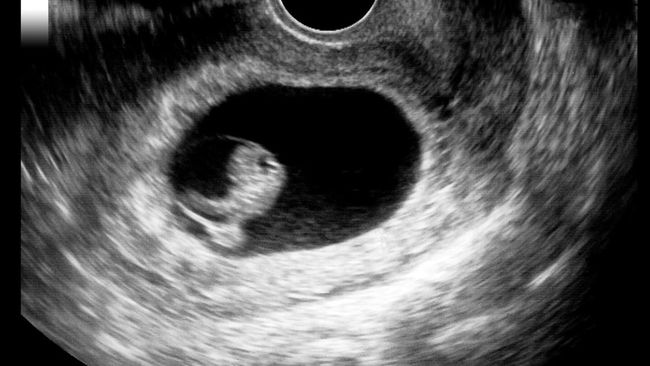

Ilustrasi (Foto: Getty Images/UrsaHoogle).